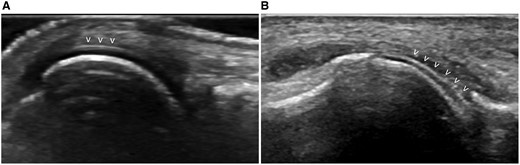

• "двойной контур" - отложение кристаллов моноурата на поверхности хряща;

Двойной контур - изображение В.

• вид "метели" или “снежной бури” - кристаллы в синовиальной жидкости сустава,